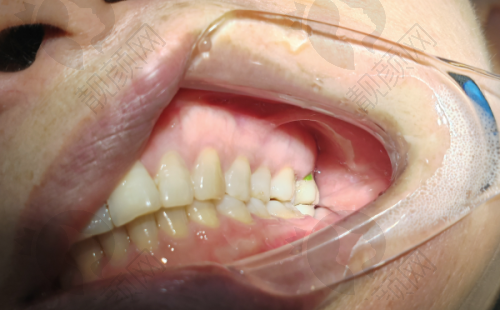

上海鼎植刘正欢种植牙实例

曾有一位患者,由于长期牙齿缺失,导致牙槽骨重度萎缩,普通的种植牙技术难以实施。刘正欢院长经过详细的检查和分析,决定为患者采用穿颧种植技术。在手术过程中,刘院长凭借不错的技艺和丰富的经验,精细操作,成功为患者植入种植体。术后,患者修复良好,牙齿功能和美观度都得到了极大的改善,对刘院长的医术赞不绝口。